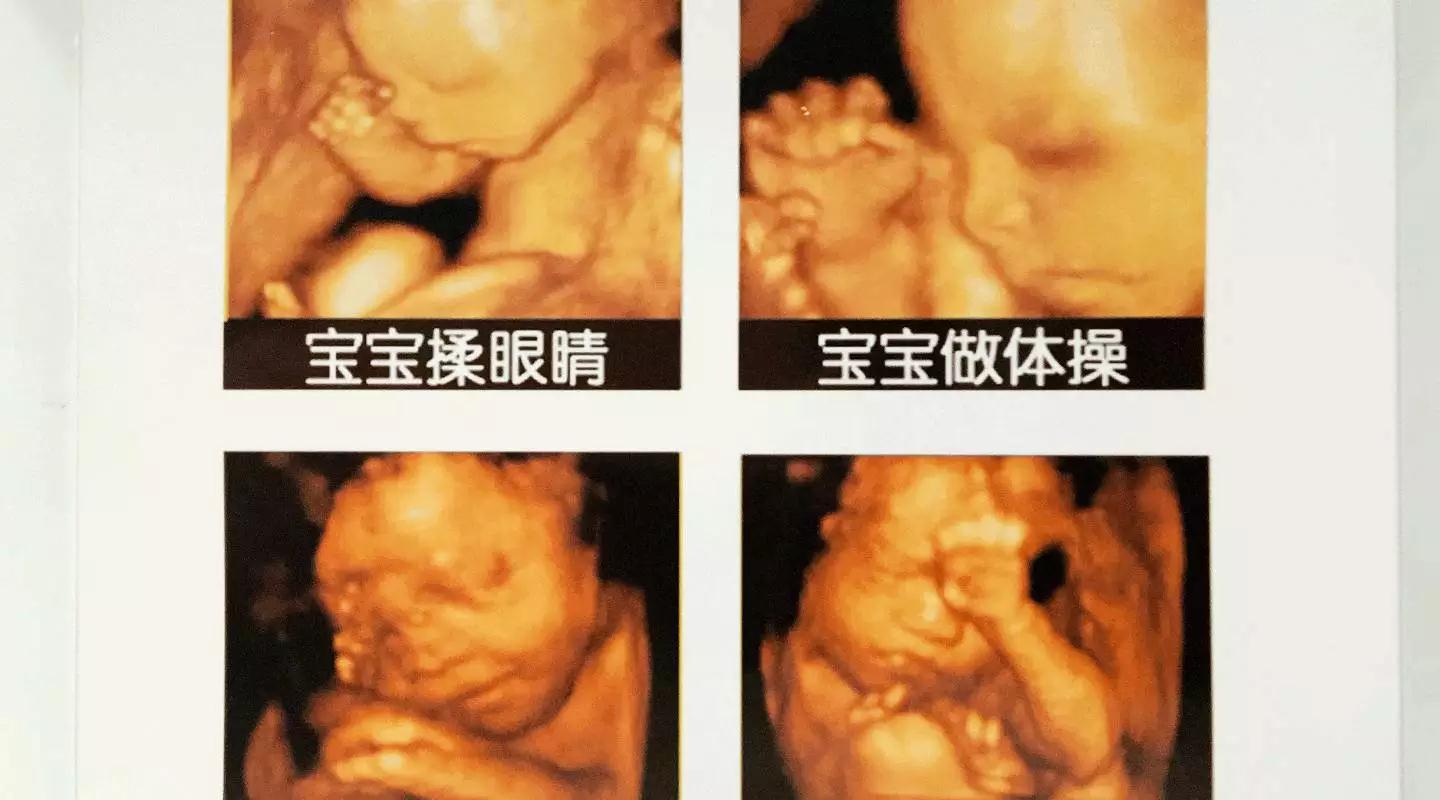

美GE不仅能提供包括腹部、血管、小器官、产科、妇科、泌尿科、新生儿和儿科等多领域的多方面的应用,而且能够显示未出生的宝宝的实时动态活动图像,为胎儿进行宫内拍“写真”和动态录像,让宝宝拥有完整的0岁相册。通过四维彩超(四维彩超),可以看到宫内胎儿打哈欠、伸懒腰、吮手指等萌萌的动作,让准爸妈们增添了安心和乐趣,不再仅仅是感觉宝宝的呼吸和运动,可以亲眼目睹宝宝的举动和乖巧容颜。还可以打印宫内高清写真,作为送给未来宝宝的珍贵礼物!